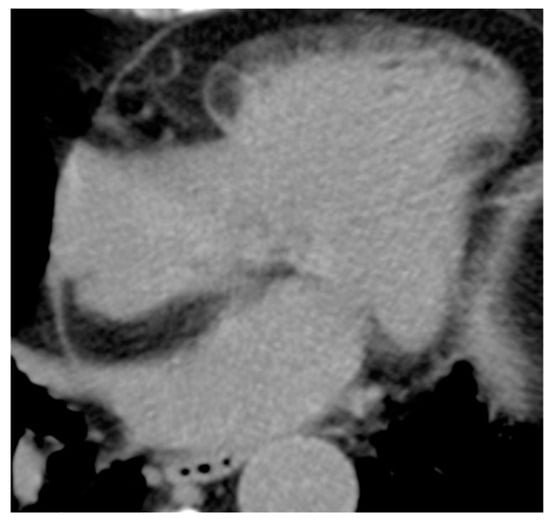

| Thrombus | Adulthood | LA, LAA (AF) LV (MI) | Asymptomatic, embolic events | Non-enhancing Intracardiac lesion | Acute: Low echodensity, rounded with smooth contours Chronic: High echodensity, linear or crescentic lesions along the endocardial surface | Low attenuation, no contrast enhancement, chronic thrombus may be calcified Usefulness of delayed CT imaging, as in the LAA stasis of blood can simulate a thrombus on early arterial images | Acute: hyper T1w and T2w Subacute: hyper T1w and hypo T2w Chronic: low T1w and T2w No enhancement. |